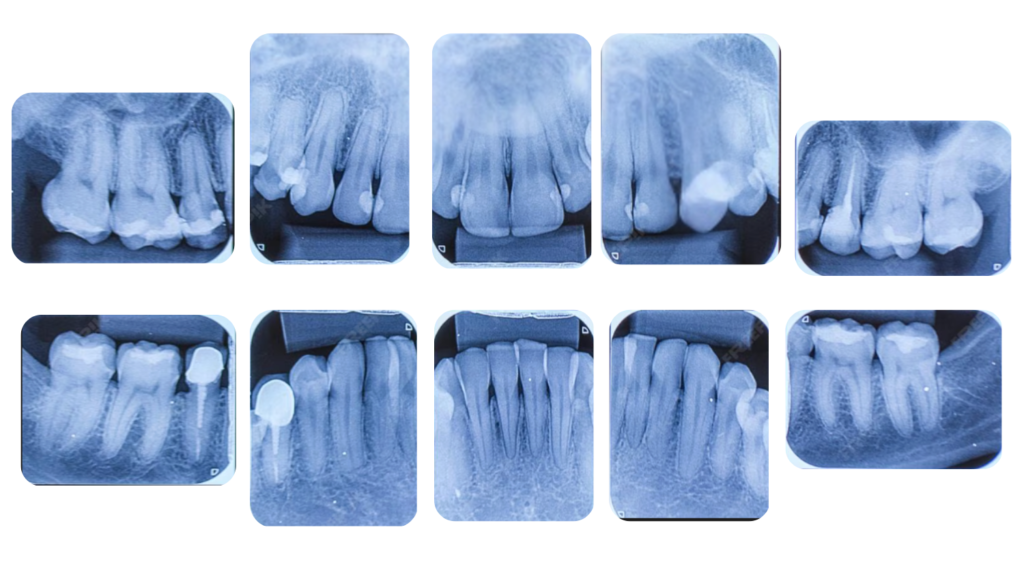

2. デンタルX線写真(10枚法)

デンタルX線写真は、特定の歯と、その周りの小さな範囲を一点集中で拡大して撮影するものです。

こちらは、歯周病が進行し、骨が溶けている箇所をより精密に確認するために行います。パノラマ写真では見逃しがちな、ごく初期の骨の変化や、歯の根っこの先の状態、歯石の付着状況などを詳細に分析できます。

歯一本一本の正確な診断と、歯周病治療の成功に直結する細かい情報の取得を可能にします。

このように、広範囲を把握する「パノラマ」と、詳細を分析する「デンタル」を組み合わせることで、あなたの歯周病の状態を診断し、最適な治療計画をご提案しています。